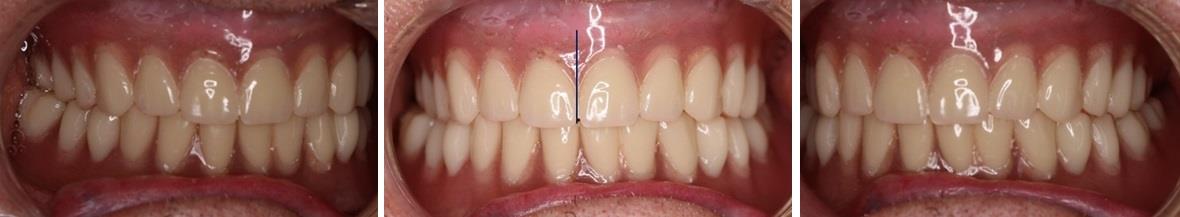

Несмотря на наличие перекрестной окклюзии при проведении функциональных проб, протезы не балансировали в полости рта и не требовали специальных гелей для улучшения их фиксации.

При смещении нижней челюсти в сторону определялось «клыковое ведение» при котором контакт был только на клыках, что характерно для оптимальной окклюзии (рис. 5). Таким образом, проведенное моделирование искусственных зубных дуг в полных съемных протезах при одностороннем сужении верхней челюсти, с учетом индивидуальных особенностей челюстей, показало эффективность предложенных лечебно-диагностических мероприятий.

Рис. 5. Клыковое ведение на полных съемных протезах